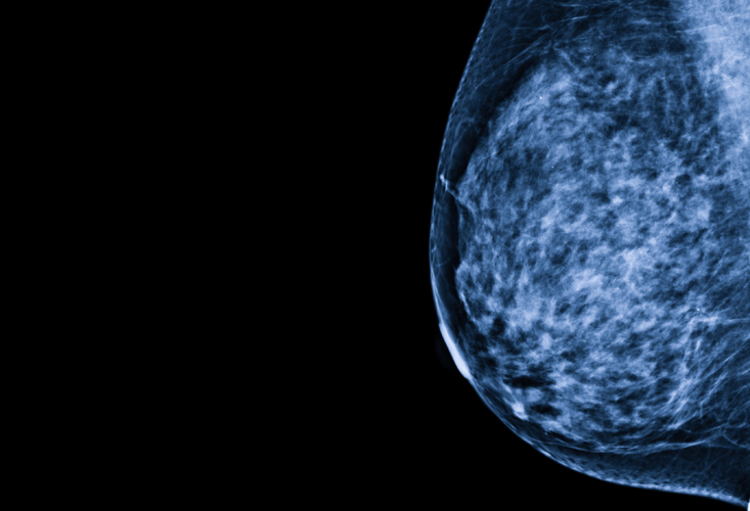

Risicoperceptie bij patiënten en artsen omtrent ductaal carcinoma in situ van de borst

Marianne, een 51-jarige kassierster, is na het zien van de ‘Pink October’-campagne overtuigd van het nut van een screeningsmammografie en laat, net als veel andere vrouwen tussen 50 en 69 jaar oud, “naar haar borsten kijken”. Op haar allereerste mammografie worden verdachte...